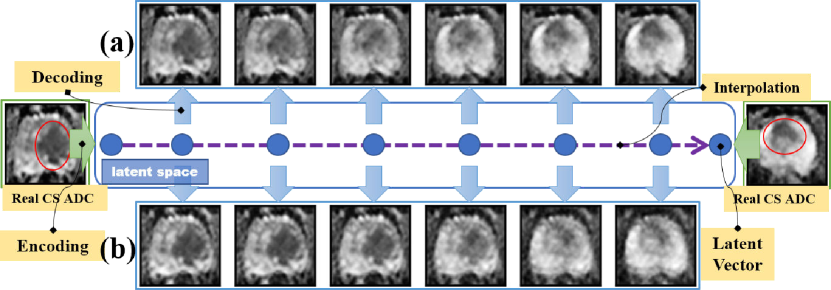

Refer to caption

Figure 1: The framework of the proposed semi-supervised mp-MRI data synthesis method which is trained based on both supervised learning (top) for enforcing a constraint of paired relationships between synthetic ADC and T2w images, and unsupervised learning (bottom) for making our method ’see’ the whole picture of the 128-d latent space so as to avoid overfitting the encodings. The green boxes describe the training targets of our method. The orange boxes connected with a dotted line share all weight parameters.

We first visually compare the synthesized images produced by the semi-supervised (employing both top and bottom parts of Fig. 1) and supervised (employing only top part of Fig. 1) methods to qualitatively demonstrate the effectiveness of our proposed semi-supervised method for addressing the overfitting problem. To better focus this analysis on only the two learning approaches, we excluded the StitchLayer and auxiliary distance maximization from the network shown in Fig. 1 for both learning approaches. To further improve the performance of the supervised method, we adopt a discriminator used in [12] which distinguishes fake pairs from real pairs for reducing the blurs in synthetic images. Both semi-supervised and supervised methods are trained based on 483483483 CS ADC-T2w pairs from the TrainSet, and latent vectors used for synthesis were obtained by two different approaches, i.e., spherical interpolation [12] and random sampling.

Figure 6: The synthesis methods generate ADC maps based on latent vectors obtained by the spherical interpolation. The ADC maps in (a) were synthesized by the semi-supervised method and the maps in (b) were synthesized by the supervised method.

The spherical interpolation approach is shown in Fig. 6. The left most and right most blue dots denote ADC encodings in the latent space derived from two real CS ADC maps. By interpolating additional dots between the two encodings, we could generate a set of new latent vectors (i.e. 2nd7thsuperscript2𝑛𝑑superscript7𝑡2^{nd}-7^{th} blue dots), based on which new fake ADC images can be generated via the decoder. A decoder learns a complete mapping relationship between latent vectors and ADC images should be able to generate smoothly transitional images from interpolated vectors between every two real images. To validate this, we purposely select two real ADC maps (i.e. the leftmost and rightmost images of Fig. 6) from the TestSet with a single CS PCa lesion locating on the right (in the leftmost image) and the top (in the rightmost image) of the prostate gland respectively. The lesions are visually darker than surrounding tissues as denoted by the red circles. Figs. 6(a) and (b) show synthesized ADC maps based on interpolations by the semi-supervised and supervised synthesizers respectively. As seen in Fig. 6(a), the CS PCa lesion is gradually and smoothly transitioned from the right to the top in the prostate gland, while the first three images of CS PCa in Fig. 6(b) are almost identical to the leftmost real image and the transition from the 4thsuperscript4𝑡4^{th} image (i.e. lesion on the right) to the 5thsuperscript5𝑡5^{th} image (i.e. lesion at the top) is sudden and not smooth.